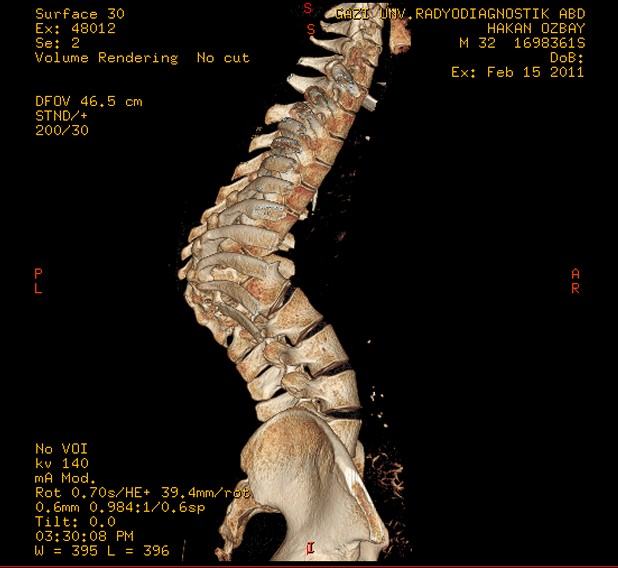

Omurga veremi sonucu kifoz oluşan hastanın ameliyat öncesi ve sonrası filmleri: